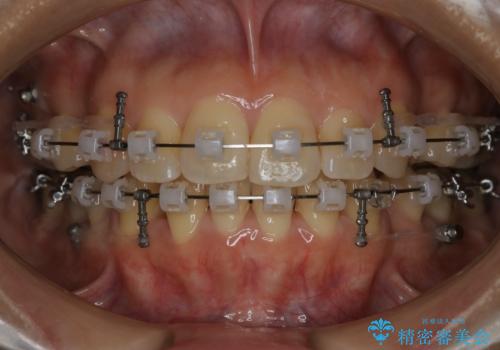

前歯を後ろに下げたい ワイヤー矯正(クリア装置)

- 前歯を後ろへ下げることを主訴に来院された患者様です。

10代の時に非抜歯でワイヤー矯正をしていました。

口元の突出感の改善や歯の移動量などを考慮し、抜歯を伴うワイヤー矯正での治療を選択しました。

抜歯を行うことで前歯を後ろへ下げるスペースを獲得し、口元の突出感や歯のガタつきを改善していきました。